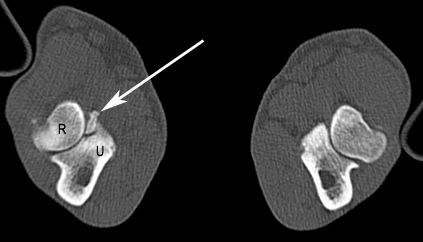

Nachdem ich bei „Oscar“ die Narkosefähigkeit geprüft hatte, haben wir einen Venenkatheter eingelegt und darüber die Narkose eingeleitet. „Oscar“ bekam einen Luftröhrentubus, damit in der Narkose die Atmung nicht behindert wird und er Narkosegase einatmen kann. „Oscar“ wurde für die Untersuchung der Ellbogengelenke in Brustlage mit gestreckten Vordergliedmaßen auf dem Untersuchungstisch gelagert und mit kontrastarmen Lagerungshilfen (z.B. Schaumstoffkeile oder Rohrisolationen) positioniert. Die reine Untersuchungszeit im CT beträgt für eine Ellbogensequenz ca. 10-15 Sekunden (120 kV, 200 mAs, Schichtdicke 0,75 mm, W 2500 L 500, Ellbogen beidseits transversal, nativ). Bei „Oscar“ fand ich auf diese Weise einen feinen Riss am inneren Kronfortsatz der Elle (Processus coronoideus medialis ulnae). Seine eigentliche Spitze war durch Entmineralisation bereits weniger röntgendicht. Als Folge dieses „Bruches“ war es zu einer Reizung des Gelenks und damit zu einer beginnenden Arthrose mit Ausbildung von Knochenspikes gekommen.

Diadnose: Abgebrochener innerer Kronfortsatz

Somit stand die Diagnose „abgebrochener innerer Kronfortsatz“ (fragmentierter Processus coronoideus medialis ulnae) als Ursache für die Lahmheit bei „Oscar“ fest. Diese Erkrankung zählt zum Formenkreis der Ellbogengelenkdysplasie und ist eine der häufigsten Lahmheitsursachen der Vordergliedmaße beim großwüchsigen Hund. Da das Belassen des abgebrochenen Kronfortsatzes die Arthrosebildung begünstigt, haben wir in der gleichen Narkose das Bruchstück arthroskopisch entfernt.